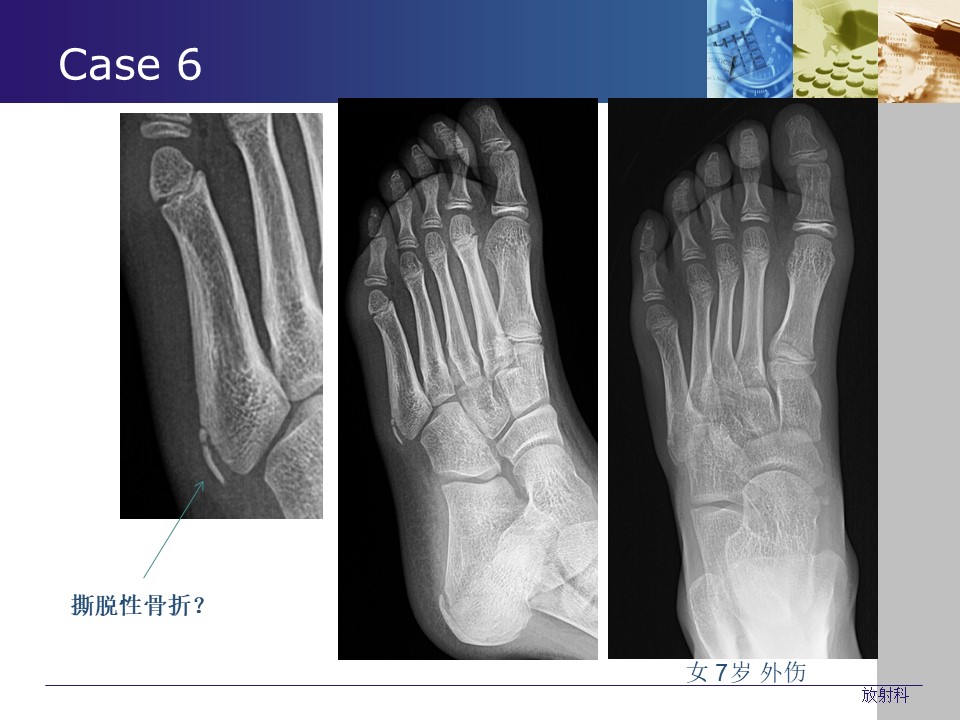

“常见生理(解剖)变异与撕脱骨折的影像学鉴别PPT” 的相关文章